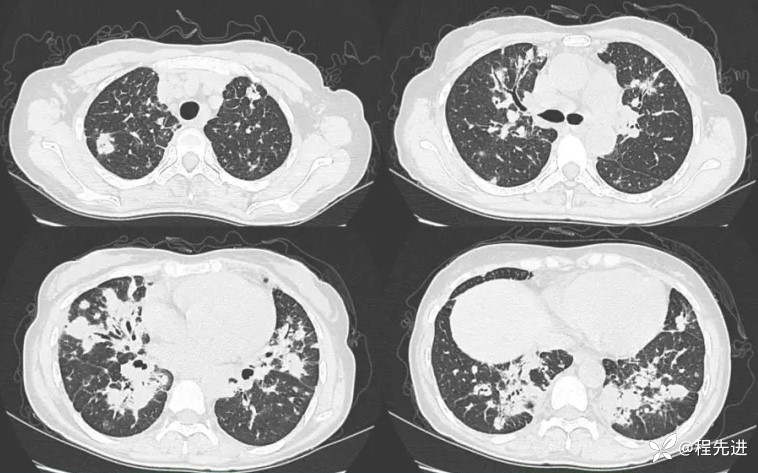

CT检查: